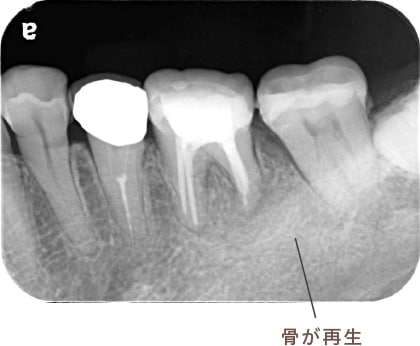

治療後病気がなくなり骨が再生した